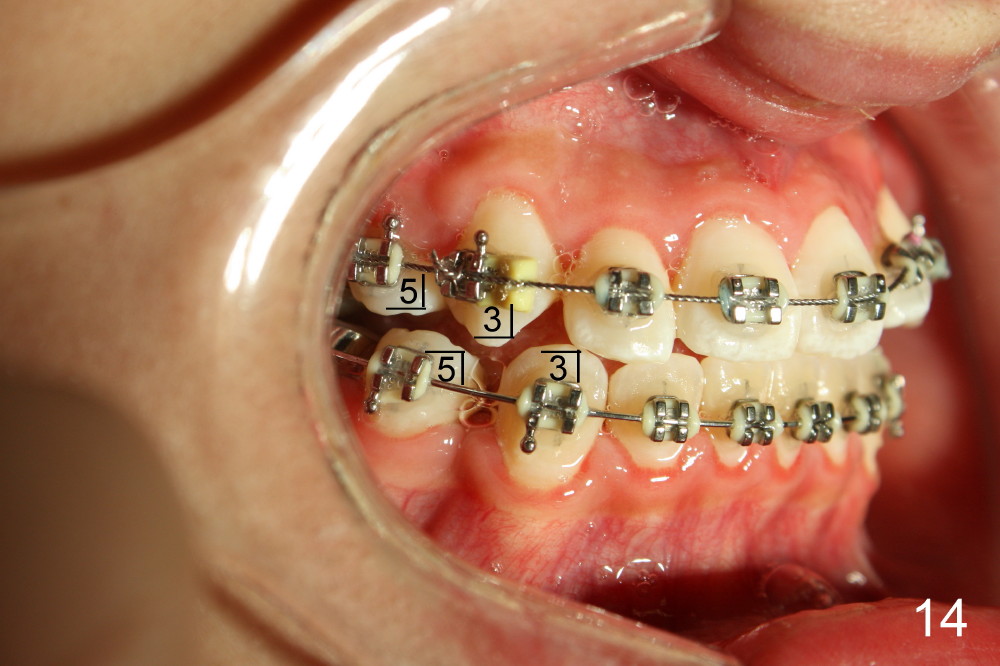

Seven months of treatment, the dental midlines coincide (Fig.13 dashed lines). Extraction spaces have been closed or being closed (Fig.13-15). UL 2 has been moved into the arch (Fig.13,15,16). But the alignment needs to be improved with arch wire sequence for a second time starting with .0175 twisted wire (Fig.13-16).